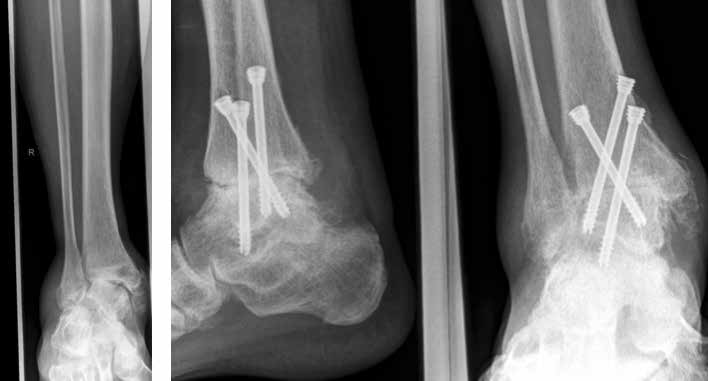

Arthrose stellt weltweit die häufigste Gelenkerkrankung dar und hat damit einen wesentlichen sozioökomischen Einfluss 1. Während 15 % der weltweiten erwachsenen Bevölkerung von Arthrose betroffen sind 2, leiden lediglich 1 % der Bevölkerung 3 bzw. 4,4 % der Arthrosepatienten 4 an einer Arthrose des oberen Sprunggelenks (OSG). Circa 80 % der Arthrosen des OSG sind ursächlich als posttraumatisch einzustufen, nur 9 % gelten als primäre Arthrosen. Dies unterscheidet die Arthrose des OSG von Coxarthrose (58 % primär) und Gonarthrose (67 % primär). 13 % treten im Rahmen systemischer Erkrankungen wie rheumatoider Arthritis, Hämochromatose, Hämophilie oder Osteonekrose auf 5 6. Die posttraumatische Arthrose des OSG wird besonders nach in Achsabweichung verheilten Frakturen (Pilon-tibiale-Frakturen, Weber-A‑, ‑B- und ‑C-Frakturen; Abb. 1a), Bandinstabilitäten des lateralen und medialen Bandapparates des OSG (Lig. fibulotalare anterius, Lig. fibulocalcaneare, Lig. fibulotibiale posterius etc.), nach rezidivierenden ligamentären Verletzungen sowie nach Gelenkverletzungen mit Knorpelschaden, „flake fractures“ oder „bone bruise“ beobachtet 7. Daher ist bei den vergleichsweise häufigen Weber-B- und ‑C-Frakturen die osteosynthetische Versorgung mittels Drittelrohrplatte und Zugschraube (Abb. 1b) sowie ggf. Syndesmosennaht mit Implantation einer Stellschraube mit millimetergenauer Reposition essentiell, um langfristig die Funktionsfähigkeit des OSG aufrechtzuerhalten und eine frühzeitige posttraumatische Arthrose zu verhindern 8.

Weiterhin führen Fehlstellungen im Rückfuß zu statischen und dynamischen Überlastungen, da sich bei Varusfehlstellung (Abb. 2a) das Zentrum der Kraftübertragung nach medial und bei Valgusfehlstellungen nach lateral verlagert 47. Die Achillessehne wirkt durch ihren Zug zusätzlich invertierend bei Varusfehlstellung und evertierend bei Valgusfehlstellung auf den Rückfuß ein 48. Möglichkeiten der operativen Therapie sind entweder die einfache Umstellungsosteotomie der distalen Tibia und Fibula als rein supramalleoläre Osteotomie mit dem Ziel einer Überkorrektur des distalen Tibiagelenkflächenwinkels von 3 bis 5° 49 oder die kombinierte Osteotomie an Bein und Rückfuß (Abb. 2b) mit oder ohne Weichteileingriff je nach Topographie der Achsfehlstellung 50. Weitere Möglichkeiten sind die Calcaneusosteotomie, meist als ergänzende Osteotomie nach Wiederherstellung der korrekten Achse (Abb. 2b) im Sinne einer Verschiebeosteotomie, um die Zugrichtung der Achillessehne zu zentrieren, und die Osteotomie der medialen Säule, die bei durch Valgusfehlstellung induzierter Abflachung des medialen Längsgewölbes indiziert sind. Hierbei werden zusätzlich korrigierende Arthrodesen des I. Strahls (Naviculo-cuneiforme-Gelenk, Tarsometatarsalgelenk) oder plantarflektierende Osteotomien (Cuneiforme I oder Metatarsale I) durchgeführt 51.

In ausgeprägten Fällen von Arthrose, oft mit Instabilität im oberen Sprunggelenk (Abb. 7), schwerwiegendem Funktionsverlust und starker Schmerzausprägung, ist nach wie vor die Arthrodese die Therapieoption der Wahl. Dadurch sollen die Achskongruenz wiederhergestellt und die Schmerzen eliminiert werden. Gleichzeitig bedeutet dieser Schritt jedoch, dass keine weitere operative Eskalation mehr möglich ist. Meist kommen die tibiotarsale oder tibiatalar-calcaneare Arthrodese zum Einsatz. Entscheidend für die Wahl des Arthrodeseverfahrens sind der Schweregrad der degenerativen Gelenkveränderungen, der Schmerz und die Stellungsverhältnisse im Subtalargelenk.

Eine Sonderform stellt die Talusnekrose dar, die ebenfalls zu schwerwiegenden Destruktionen und Achsfehlstellungen im OSG führt. Das Mittel der Wahl im fortgeschrittenen Stadium (Abb. 8a) ist hier die Arthrodese des OSG und des unteren Sprunggelenks (USG) mittels Arthrodesennagel (Abb. 8b).